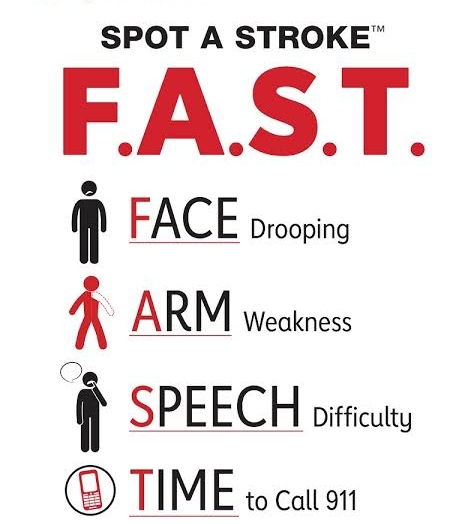

Once there’s “FAST” which stands for

F- FACE DEVIATION

A- Weakness of the ARM

S- Change in SPEECH

T- TIMING which are all of SUDDEN ONSET

You have to quickly bring the person to the nearest hospital. This is not the time for prayer house, traditional healers, Patent medicine dealers, pharmaceutical shops, native doctors, etc.

Always remember “FAST“

Quickly rush the person to the hospital.